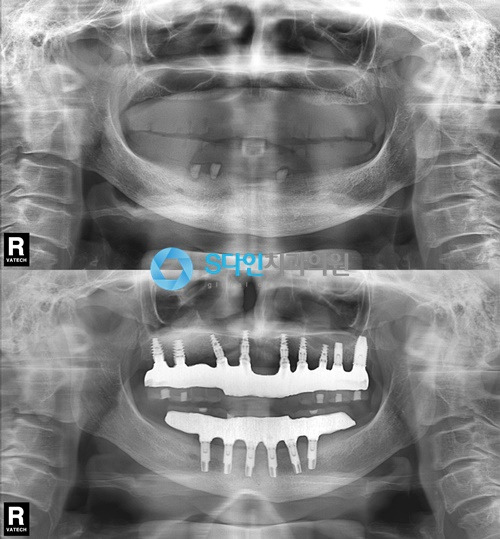

임플란트는 최대한 자연치아와 같은 기능과 심미적인 부분까지 충족해야 하기 때문에 전악임플란트처럼 여러 개의 임플란트를 식립해야 하는 경우에는 잇몸뼈 상태, 식립 시 각도 및 깊이, 간격, 교합, 구강구조 등 좀 더 다각적인 진단과 섬세한 기술이 필요합니다.

특히 이미 치아를 상실한 상태라 잇몸뼈가 좋지 않은 경우가 많아 잇몸뼈를 이식해야 하는 등의 과정이 필요하죠. 시간이 많이 걸리는 만큼 환자의 건강상태 및 협조도도 충분히 고려되어야 합니다.

- 고정성 전체 임플란트: 대부분의 치아를 상실했더라도 잇몸뼈가 남아 있다면 고려해볼 수 있는 방법으로 임플란트가 잇몸뼈에 단단히 고정이 되기 때문에 고정력이 좋고 자연치아의 80% 정도까지 저작기능이 회복됩니다. 위아래 턱뼈와 치아의 맞물림 상태, 잇몸뼈 상태 등을 고려해야 하며 일반적으로 상악엔 6~7개, 하악엔 7~8개의 임플란트를 식립 합니다.